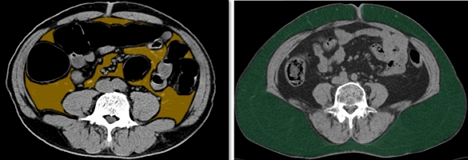

처음 CT를 찍고 평균 3.3년 후 다시 CT를 찍었을 때 37.5%에서 심장혈관의 석회화가 의미 있게 증가한 것이 관찰됐다. 기존에 알려진 심혈관 질환의 위험인자를 보정한 후에도 비만한 경우, 허리둘레가 큰 경우, 내장지방이 피하지방보다 많은 경우 심장혈관의 석회화가 유의하게 증가했다.

특히, 내장지방이 피하지방보다 30% 이상 많은 경우 가장 강력한 위험인자로 그렇지 않은 경우보다 심장혈관 석회화가 증가할 위험이 2.2배 높았다.

그 결과, 비만군이나 과체중 또는 복부비만군 뿐만 아니라, 정상 체중에서도 내장지방이 피하지방보다 30% 이상 많은 경우 심장혈관의 석회화가 증가할 위험이 1.9배 증가했다.

이는 일반적인 외관상 비슷한 정도의 비만 정도여도, 심지어 외관상 비만이 아니어도 체내 지방의 분포(distribution of body fat)가 심혈관 질환에 영향을 준다는 것을 보여준 연구이다.